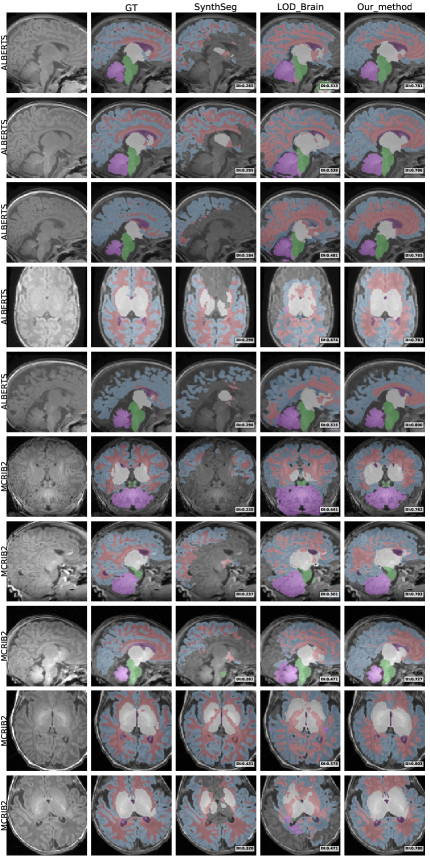

5.2 Qualitative comparisons on raw infant data

To provide a clear visual assessment of segmentation performance, we present a diverse set of qualitative results obtained using different methods. Figs 4 and 5 illustrate a side-by-side comparison between the competing approaches and the silver-standard ground truth generated by Infant FreeSurfer. Specifically, we highlight the 30 most discordant MRI volumes, identified as those exhibiting the highest variance in DICE scores across the evaluated methods when compared to Infant FreeSurfer segmentations. By focusing on these challenging cases, we enhance the visibility of key differences in anatomical structure delineation, allowing for a more insightful comparison of method effectiveness.

This visualization strategy ensures that performance disparities between compared approaches are clearly distinguishable, providing an intuitive and informative perspective on the strengths and limitations of each method, including our proposed solution.